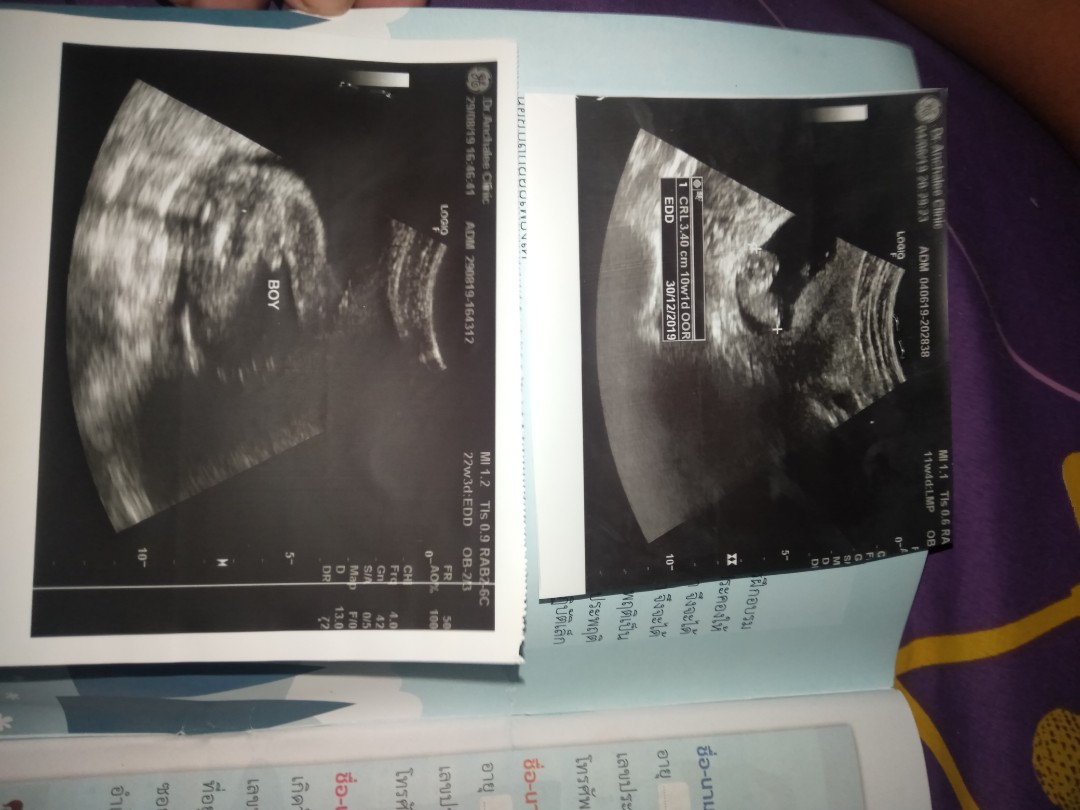

ชายจ้า